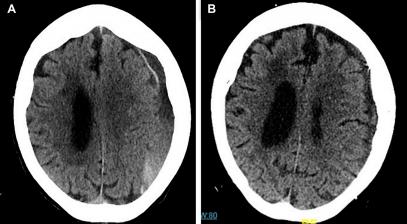

栓塞术前术后对比

脑膜中动脉栓塞术

早期人们对达到手术标准的患者在钻孔引流术前或术后进行脑膜中动脉栓塞术,以减少术后复发,结果显示所有患者均没有复发;钻孔引流解决了占位效应,MMA栓塞解决了出血来源的问题,做到了“标本”兼治。后期人们对没有采用手术治疗的患者进行MMA栓塞治疗,已经出现的硬膜下血肿随着时间的推移会逐渐吸收,并可阻止血肿扩大。之后人们开始在更大范围内进行尝试,结果似乎还不错;最近的一项有关MMA栓塞治疗CSDH的meta分析显示MMA栓塞相对传统手术治疗具有明显的优势,MMA栓塞组的血肿复发率明显低于未栓塞组(2.1% VS 27.7% ,OR 0.563)。